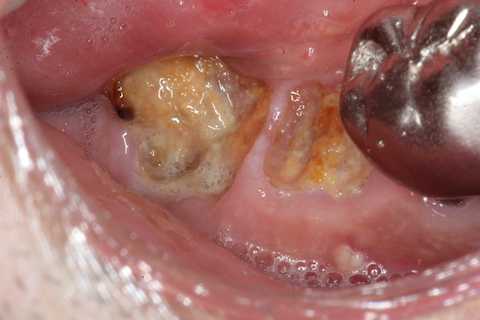

今日も野戦病院シリーズ26(CK破折) 2025.10.25